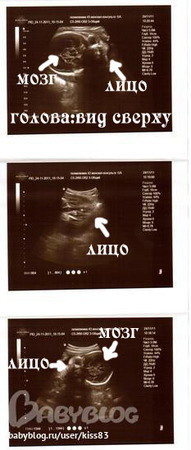

Но записана была к др врачу,а не к тому,что ходила в 12-14нед(добрая).Зато у этой(более строгая и ппротивная) в кабинете аппарат 3-4Д УЗИ.Порадовала меня показателями-все в норме,грит странно,почему плаценту в 21 нед на 3см посчитали низкой?что это норма.(Но я сравнила с результ снохи-мы на одном сроке с ней и в один день у одного и того ж доктора делали УЗИ)у нее 5 см было),так вот...сейчас у меня 4см.Но эт уже хорошо.Показала крупно писюльку)))Подтвердила что дееевочка)))Попросила ее фото сделать-прикиньте,150 р грит.Ну лан....отдала.Хотя на фото ну ниччче не понятно(((

Как непонятно, вон же на второй прям личико видно)) хорошая фотка! Хорошо, что купила)

Аа вон вижу, расшифровали ниже тебе уже)